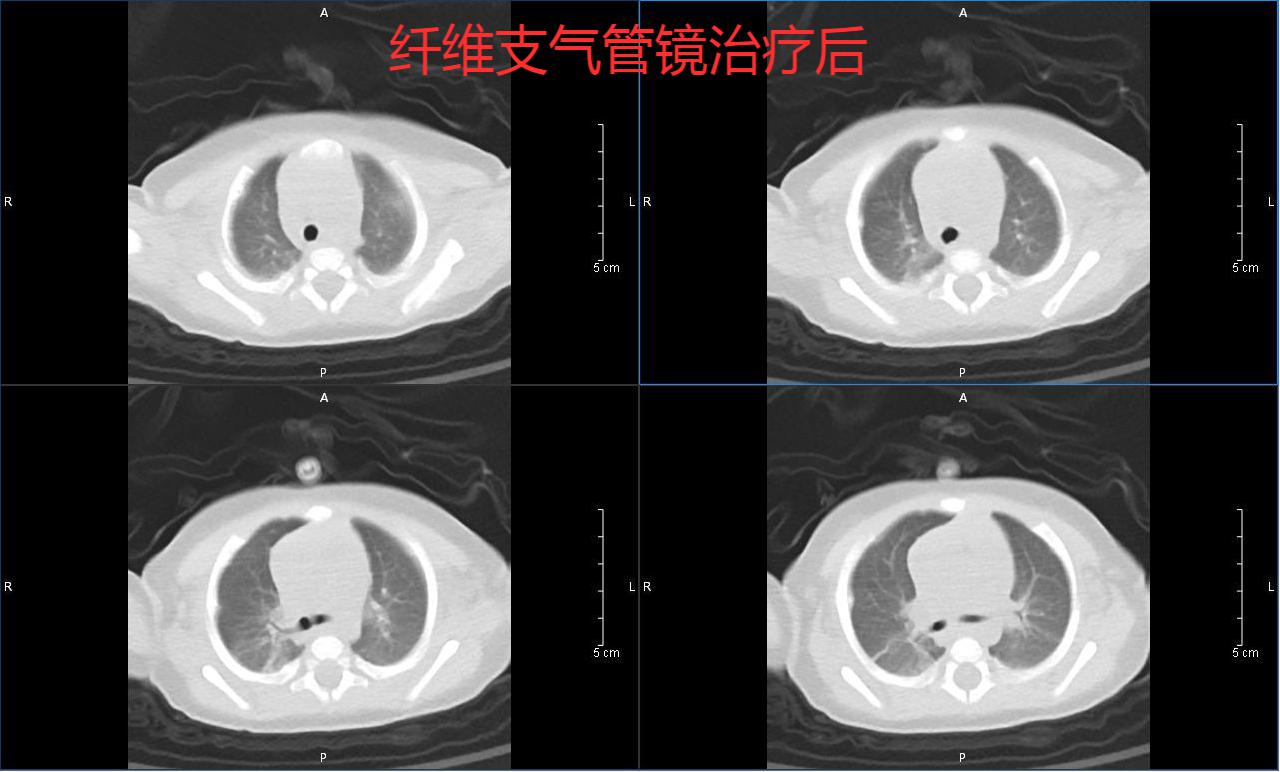

治疗后

由于患儿右肺不张及肺部大量炎症不容乐观,可能导致患儿再次出现呼吸、心力衰竭,为进一步清除肺部炎症,韦瑞含副主任医师给患儿进行了纤支镜检查及肺泡灌洗。7天后当小滢双肺病灶明显吸收,疗效显著,于1月18号转普通病房继续治疗。后经过近半个月的积极治疗,小滢终于康复出院。